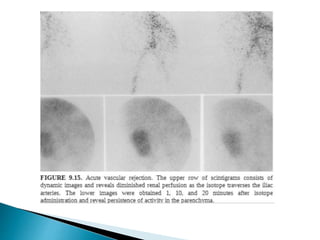

 Hyperacute rejection

 Doppler usg shows little or nil cortical blood flow

 Radionuclide studies show complete absence of perfusion or

tubular accumulation

 Angiography : total or near total lack of filling of vessels.